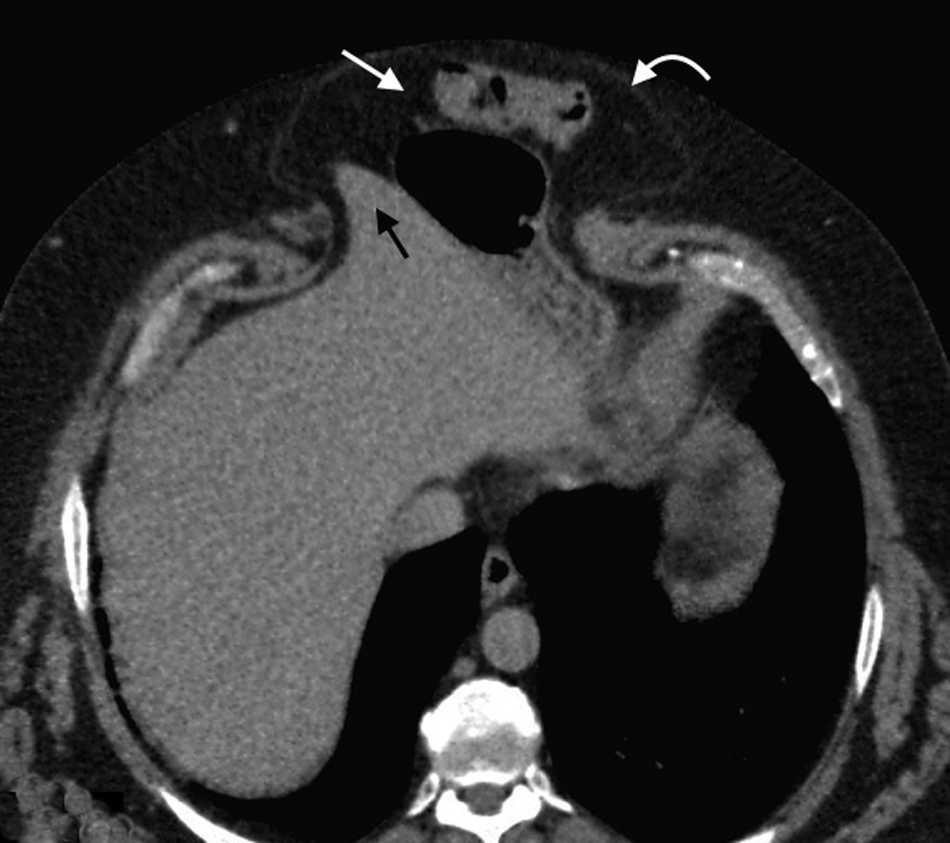

El contenido est?? relacionado con los diferentes sitios de debilidad de la pared. A nivel epig??strico se encuentra una herniaci??n del antro g??strico, del l??bulo hep??tico izquierdo (fig. 14) o de la ves??cula biliar (fig. 15). Por su parte, dentro de las umbilicales puede haber grasa peritoneal, asas intestinales, implantes metast??sicos (n??dulo de la hermana Mar??a Jos??) (fig. 16) o l??quido asc??tico (fig. 17). En la hernia de Spiegel suele visualizarse grasa y asas intestinales, mientras que las obturatrices muchas veces son descubiertas porque el paciente presenta un cuadro de obstrucci??n intestinal mec??nica que ayuda al diagn??stico. En cuanto a la lumbar, se puede herniar grasa, el polo renal o el l??bulo hep??tico derecho (fig. 18). En el caso de la inguinal, esta tiene un contenido muy variado, aunque la grasa peritoneal y las asas son los m??s frecuentes (fig. 19). Adem??s, puede herniar ??rganos intrapelvianos, como la vejiga (cistocele) (fig. 20) o el ap??ndice (hernia de Amyand)20 (fig. 21), y si se produce la herniaci??n del ap??ndice dentro del canal crural, se denomina hernia De Garengeot9 (fig. 22). Finalmente, en las eventraciones se observan asas de intestino delgado y grueso, ri??ones trasplantados (fig. 23) y vejigas (fig. 24).